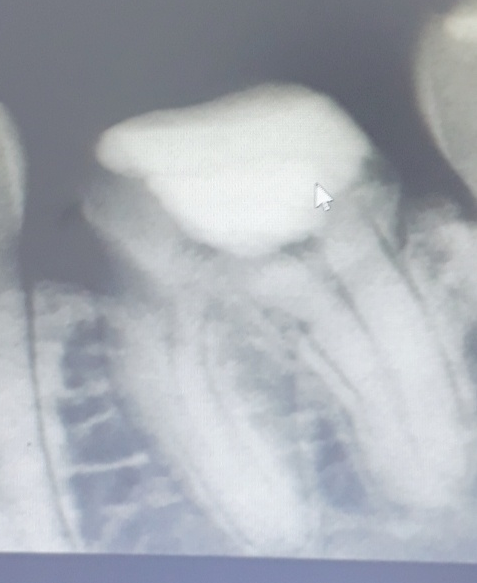

(이사진은 B병원에서 씌운 크라운)

A병원에서 어렸을때 크라운 씌운게있었는데요 (아무문제없이 치통도없고 잘지냈음)

B병원갔더니 너무 어렸을 때 한 거라 뿌리 모양이랑 안맞아서 교체하시자고해서

그대로 그냥 크라운 교체만 했습니다

B병원에서 신경치료를하지않은 치아였는데 신경치료 한줄알고 교체만하셨습니다

치통이 너무심해져서 다시찾아갔더니 답이없다 발치 혹은 임플란트해야한다 예약하시겠냐 하셔서;;

근데 C병원에서 치아 x레이 찍은거보더니

치료를 왜 이렇게했지?? 왜 신경치료를 하지도않고 이래놨지.. 치료 하다말았어요?? 상태가이상한데.. 신경다죽소 뿌리끝에 염증있어서 이거 치료빨리해야할듯요

라고하셨습니다.. 그래서 신경치료 예약을 잡아두긴했는데

의사선생님들이 보기엔 이렇게 사진만봤을때 재치료가 가능해보이나요?